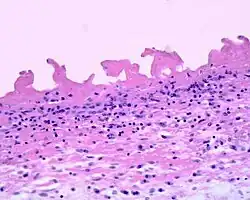

Fibrinous pericarditis is an exudative inflammation. The pericardium is infiltrated by the fibrinous exudate. This consists of fibrin strands and leukocytes. Fibrin describes an amorphous, eosinophilic (pink) network. Leukocytes (white blood cells; mainly neutrophils) are found within the fibrin deposits and intrapericardic. Vascular congestion is also present. Inflammatory cells do not penetrate the myocardium (as is seen with other presentations of pericarditis), and as a result, this particular variant does not present with diffuse ST elevation on ECG (a classic sign of pericarditis known as stage I ECG changes which are seen with other causes)[1] because the inflammatory cells do not penetrate the myocardium. To naked eye examination, this pathology is referred to as having a "Bread and Butter Appearance".